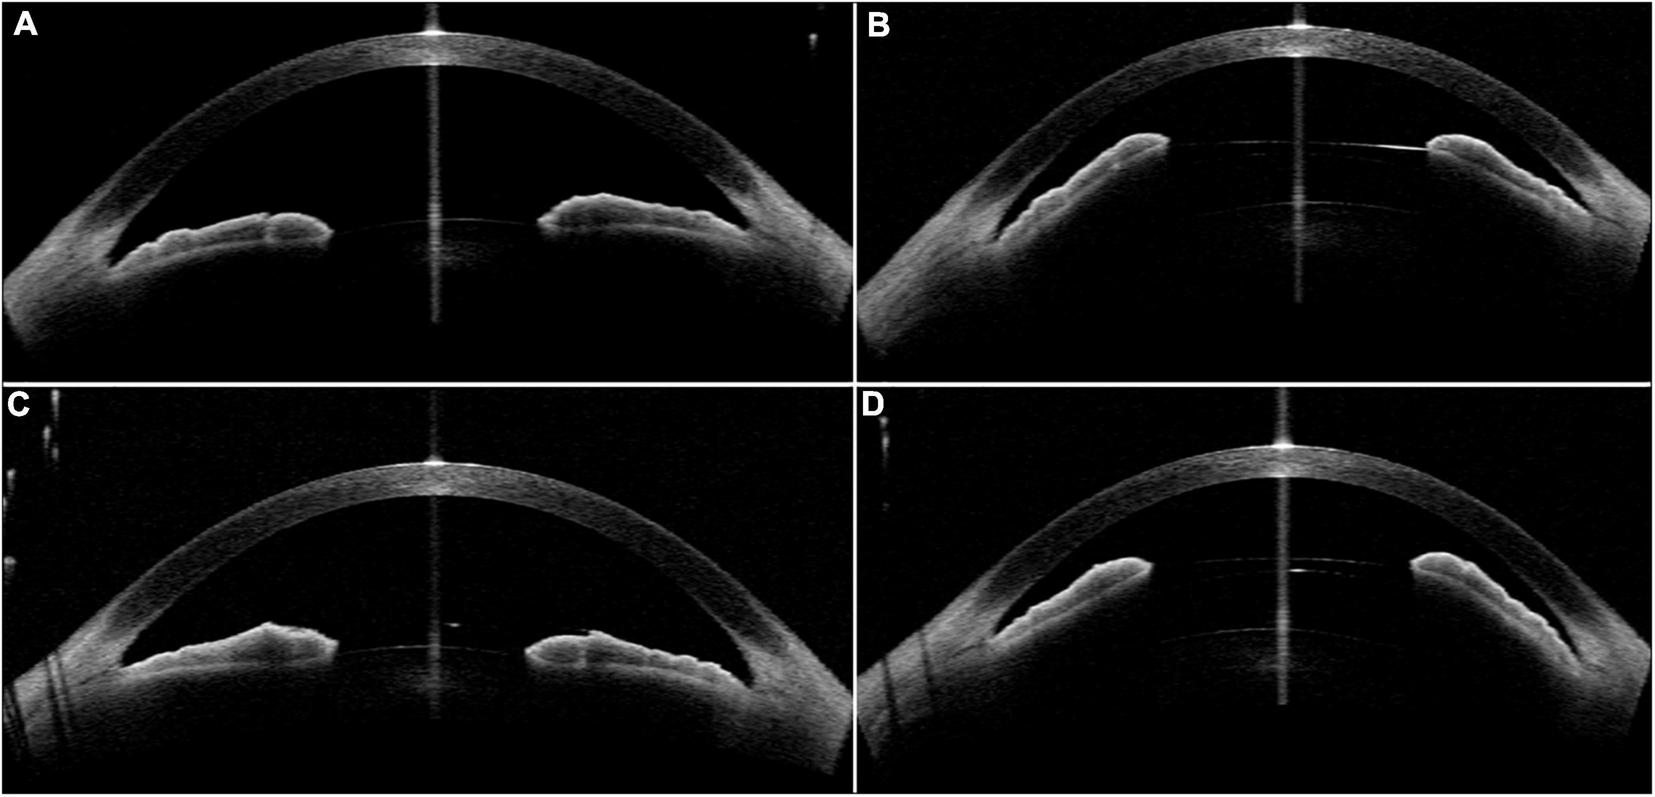

FIGURE 5

Case 2: (A,C) Convex shape iris before surgery; (B,D) high vault was shown in both eyes 1 month after ICL implantation. (Row 1: right eye; Row 2: left eye).